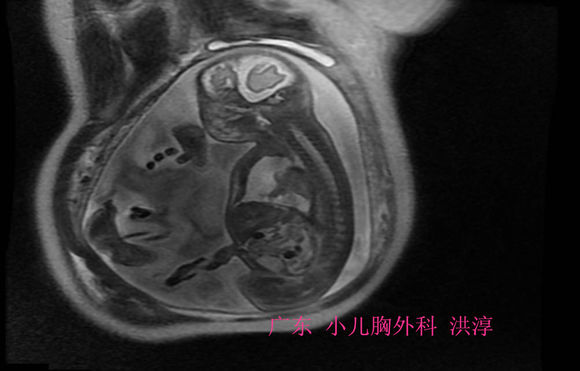

2.产前MR:MR可清楚显示肺的容积、肺发育不良的程度及胸腔积液时肺与胸腔的比率,有利于临床医生对胎儿的预后作出判断评估。对FHT在MR检查的T1相,显示为低信号,而在T2相显示为高信号,可根据所在部位与周围邻近的器官相关性作出诊断和分析。